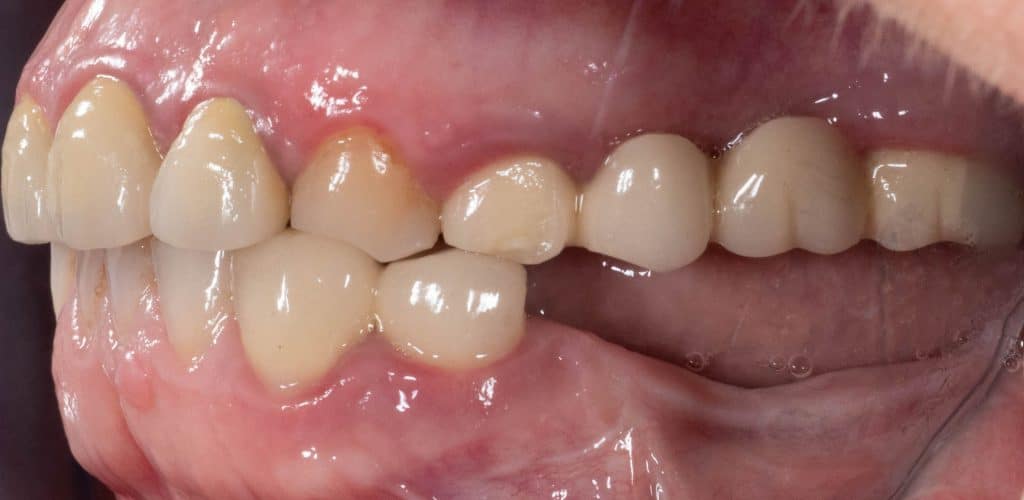

Initial clinical situation- Lateral view

Initial clinical situation- Detail of the area